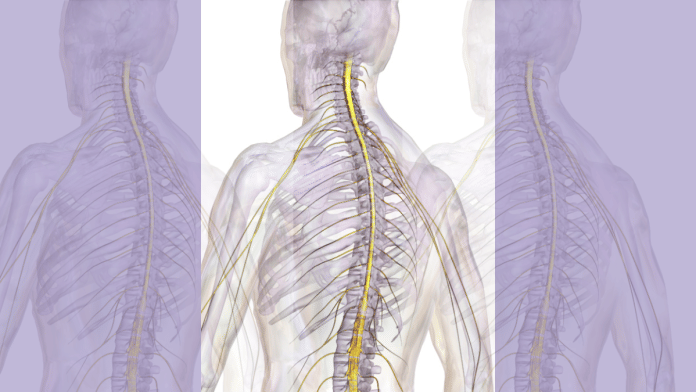

New Delhi: Researchers at the Cedars-Sinai Medical Centre in Los Angeles have identified a previously unknown repair mechanism in the spinal cord that could transform treatment for spinal injuries, strokes and neurological diseases, such as multiple sclerosis.

The discovery, published in the journal Nature on 17 December, centres on astrocytes—support cells in the brain and spinal cord—that actively drive tissue repair even when located far from the site of injury.

These “lesion-remote astrocytes” release a protein called CCN1 that signals immune cells to efficiently clear debris left behind by damaged nerve fibres, according to findings from mouse models. Without this crucial signal, inflammation spreads and recovery is significantly impaired.

Importantly, researchers found evidence of this mechanism in humans with spinal cord injury and multiple sclerosis tissue samples, highlighting astrocytes as an underappreciated target for therapies.